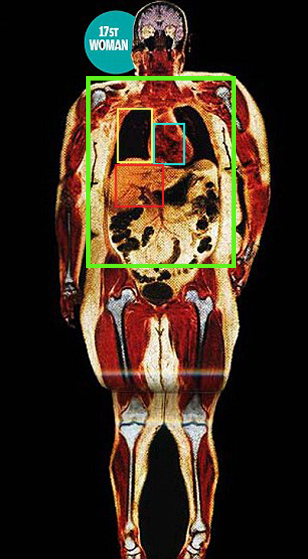

Images with red objects have the red object as the heart. Of note, the sternum does not completely cover the heart, the intercostal spaces are greater than the ribs, and on the silhouette, the heart is 9.52% of the boxed area.